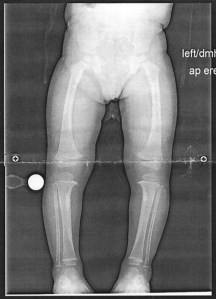

Andrea was given copies of the before and after x-ray of Malachi’s legs. Here is a picture of the straight legs in December.

December 23, 2015. Malachi’s legs a healed!

Again, in the first X-ray, Malachi’s knees are buckling outwards. In this picture they are in the proper location. Just a month earlier, while at Disney, Malachi’s legs are still visibly crooked and bent outward. I cannot say that in the last 30 days that we made Malachi wear the braces any more or less than we previously had. What I believe is that God brought healing to Malachi’s life and his legs. Not every healing is instantaneous. Some healing involve seven months of wearing leg braces. Regardless, we believe that the Great Physician was (and is) at work in Malachi’s life!